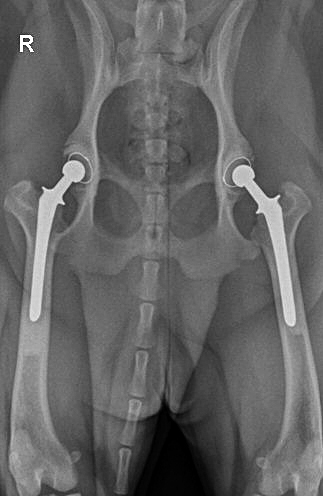

¿Cuál es tu prediagnóstico?